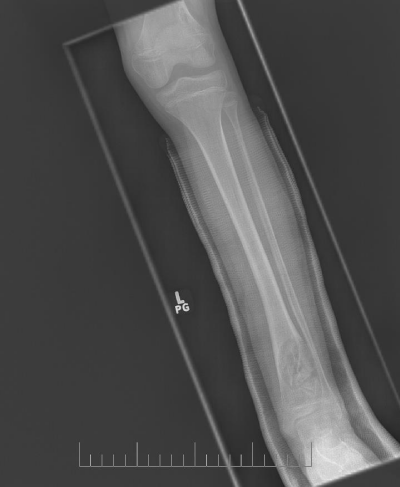

A 10-year-old female presented with left lower leg pain that had progressively increased over the duration of 1 year. On physical examination, tenderness was elicited on palpation of the distal tibia. Routine laboratory testing was normal. X-Ray was performed and revealed a lytic lesion with sclerotic margins in the left lower tibia (Figure 1). MRI was subsequently performed, demonstrating a left lower tibia lesion with low signal intensity on T1 weighted images (Figure 2), and high signal intensity on T2 weighted images (Figure 3). Pathology of the tumor revealed a diagnosis of a CMF. She was treated with curettage and autologous bone grafting (Figure 4). Post op eratively the left leg was immobilized with a plaster cast with restricted weight bearing (Figure 5). Follow up X-ray after 5 years demonstrates no tumor reoccurrence (Figure 6, Figure 7).

Figure 1: Initial lateral X-ray of the left ankle.

Imaging is crucial to the diagnosis of this tumor. On X-ray the tumor appears as a space occupying radiolucent osteolytic lesion with sharp and well-defined margins (Figure 1). The margins are noted to be sclerotic (Figure 8) the tumor has no soft tissue component (Figure 9). There is no matrix calcification or visible periosteal reaction (Figure 10).